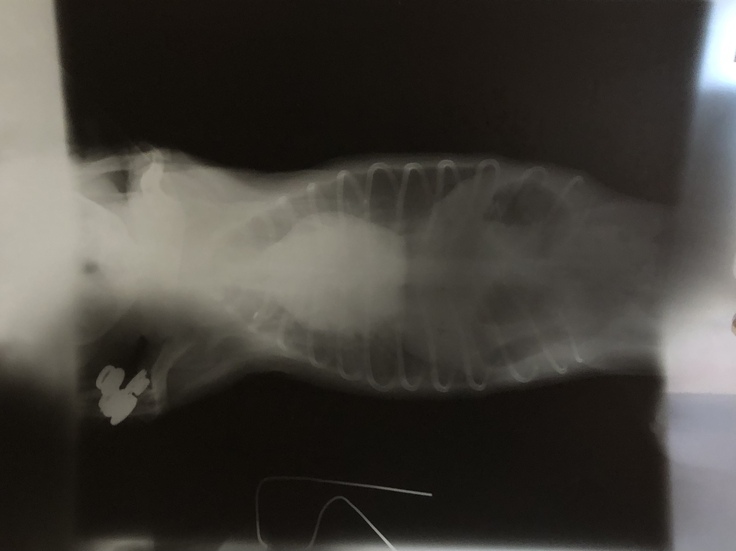

肺水腫を起こした際のレントゲンです。